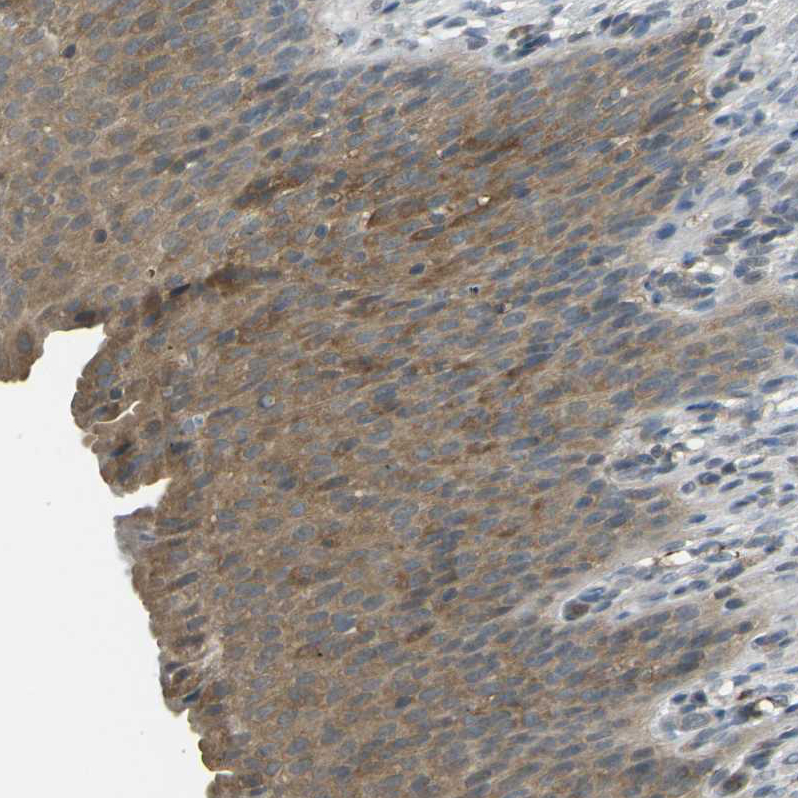

Immunohistochemical staining of human cerebral cortex shows moderate cytoplasmic positivity in neurons.